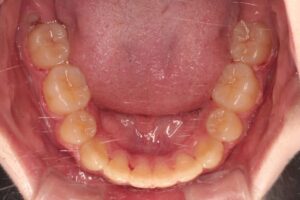

前歯部が反対咬合になっており、上顎左側犬歯が歯列に収まりきらず凸凹しています(叢生)。上顎の叢生が左側に偏在しているため上顎歯列の正中が左偏しており上下顎歯列正中が一致していません。

前歯部反対咬合、叢生、上下顎歯列正中の不一致はいずれも改善しました。側面の口腔内写真から1歯対2歯咬合も達成されており機能的にも問題ありません。